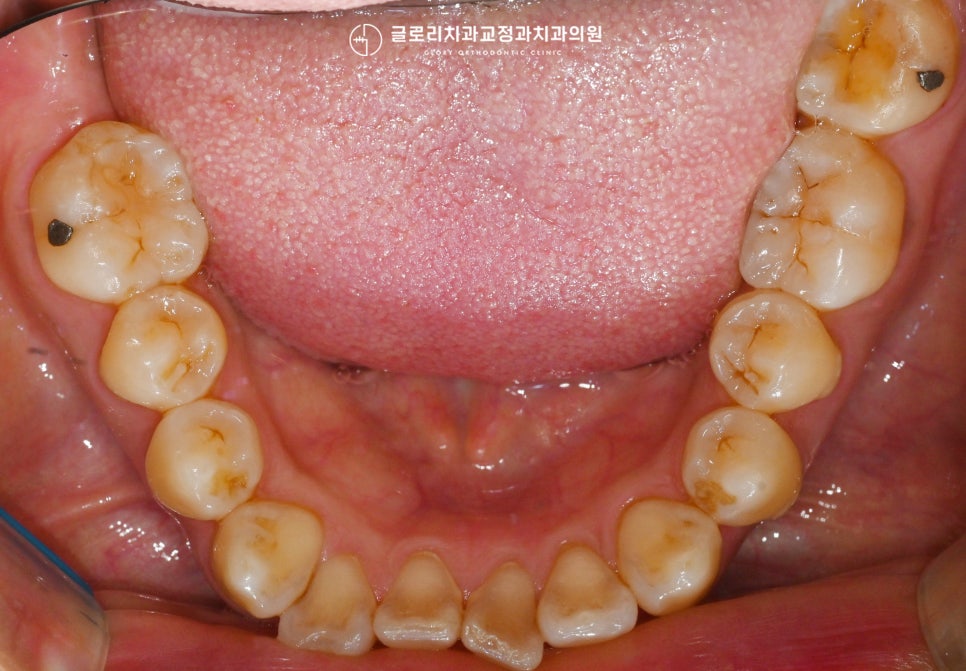

2. 어금니 부분교정

이외에도 다른 곳들은

문제가 없는지 살펴보았습니다.

구강 전반으로 조금씩 틀어짐이나

총생 문제들은 찾아볼 수 있었지만,

환자께서는 딱 이곳만 개선 받길 원하셨는데요.

이러한 의견을 수렴하여

저희 중화동 치과 에서는 어금니 부분교정을

도와드리기로 했습니다.